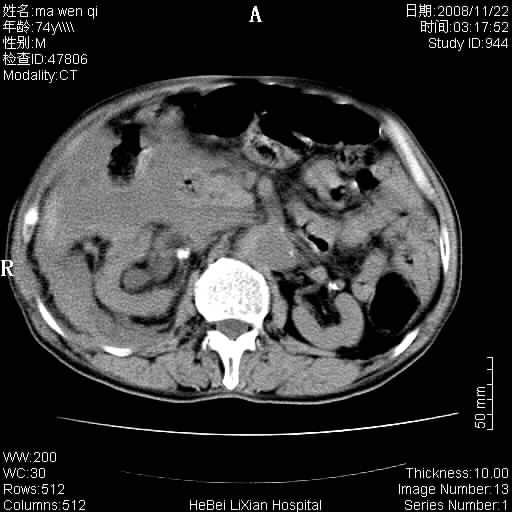

患者男 74岁.突然昏迷,休克6小时.血压70/30,头颅ct未见异常,既往体健.

补充病史,保留导尿10小时,尿袋内只有少许尿液,患者于住院后15小时后去世.

腹主动脉、双侧髂动脉夹层动脉瘤破裂出血进入腹腔。

1)考虑双侧髂动脉瘤并右侧动脉瘤破裂出血,右侧腹膜后及腹腔积血。2)双侧腹股沟疝。

1)考虑,腹主动脉、双侧髂动脉夹层动脉瘤破裂伴右侧腹膜后及腹腔积血。2)双侧腹股沟疝。

1)考虑胸、腹主动脉、双侧髂动脉瘤并右侧动脉瘤破裂出血,右侧腹膜后及腹腔积血。2)双侧腹股沟疝。